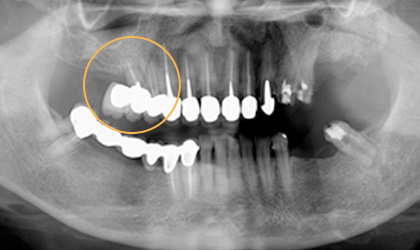

懸臂牙橋導致牙齒斷裂 ( 對側無牙 )